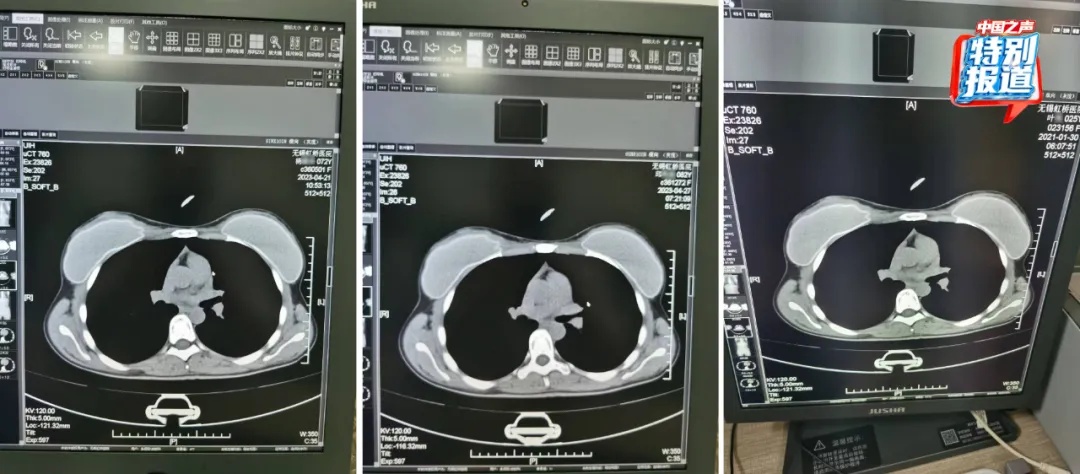

近日,无锡虹桥医院涉嫌骗保事件有了新情况。令人震惊的是,25岁、72岁和62岁三人的CT片几乎一模一样。这一发现无疑是此次涉嫌骗保事件的关键疑点。CT片本应依据不同个体的身体状况呈现出较大差异,而如此相似的结果很难不让人怀疑其中存在违规操作。这一事件的曝光,让无锡虹桥医院被推到舆论的风口浪尖,有关部门必然会深入调查,以确定医院是否存在利用虚假CT片等手段骗取医保的恶劣行为。

25岁72岁62岁三人CT片几乎一样 “无锡虹桥医院涉嫌骗保”最新进展来了△72岁的杨某某、62岁的邱某某与25岁的叶某,三人的片子几乎一模一样